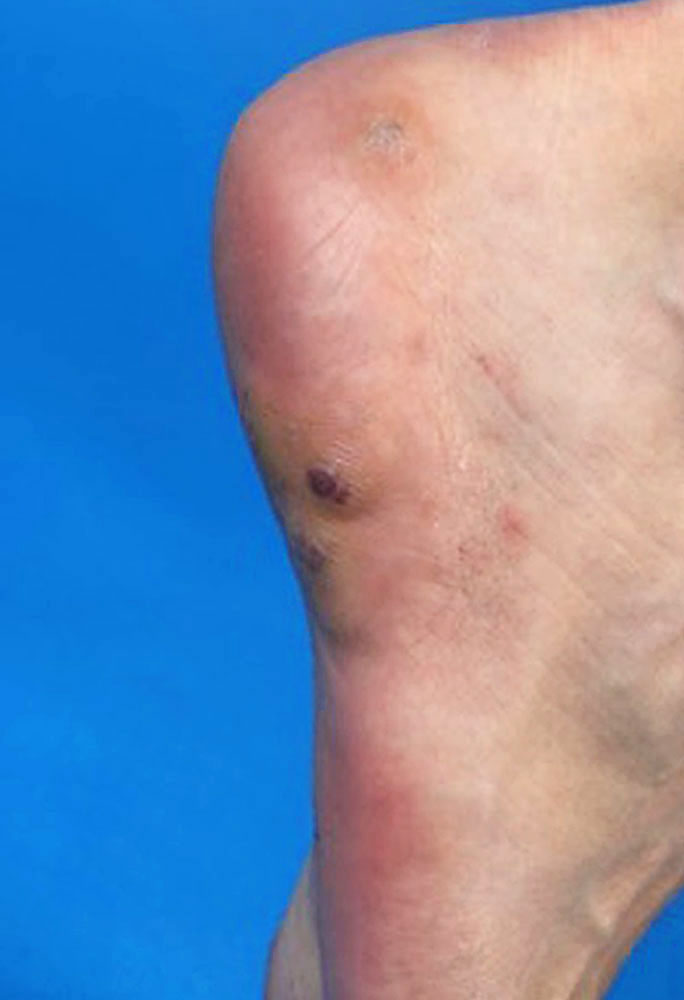

Das Maffucci-Syndrom ist charakterisiert durch multiple Enchondrome, oft sichtbar als umschriebene derbe Auftreibungen an Fingern und/oder Zehen in Kombination mit Spindelzell-Hämangiomen. Synonym: Enchondromatosis Ollier-Maffucci.

Die Gefäßveränderungen beim Mafucci-Syndrom sind multifokale, derbe, bläulich-rötliche, berührungsempfindliche Gefäßknoten der Subkutis („Spindelzell-Hämangiome“), die einer venösen Malformation ähneln, jedoch histologisch von dieser zu unterscheiden sind.